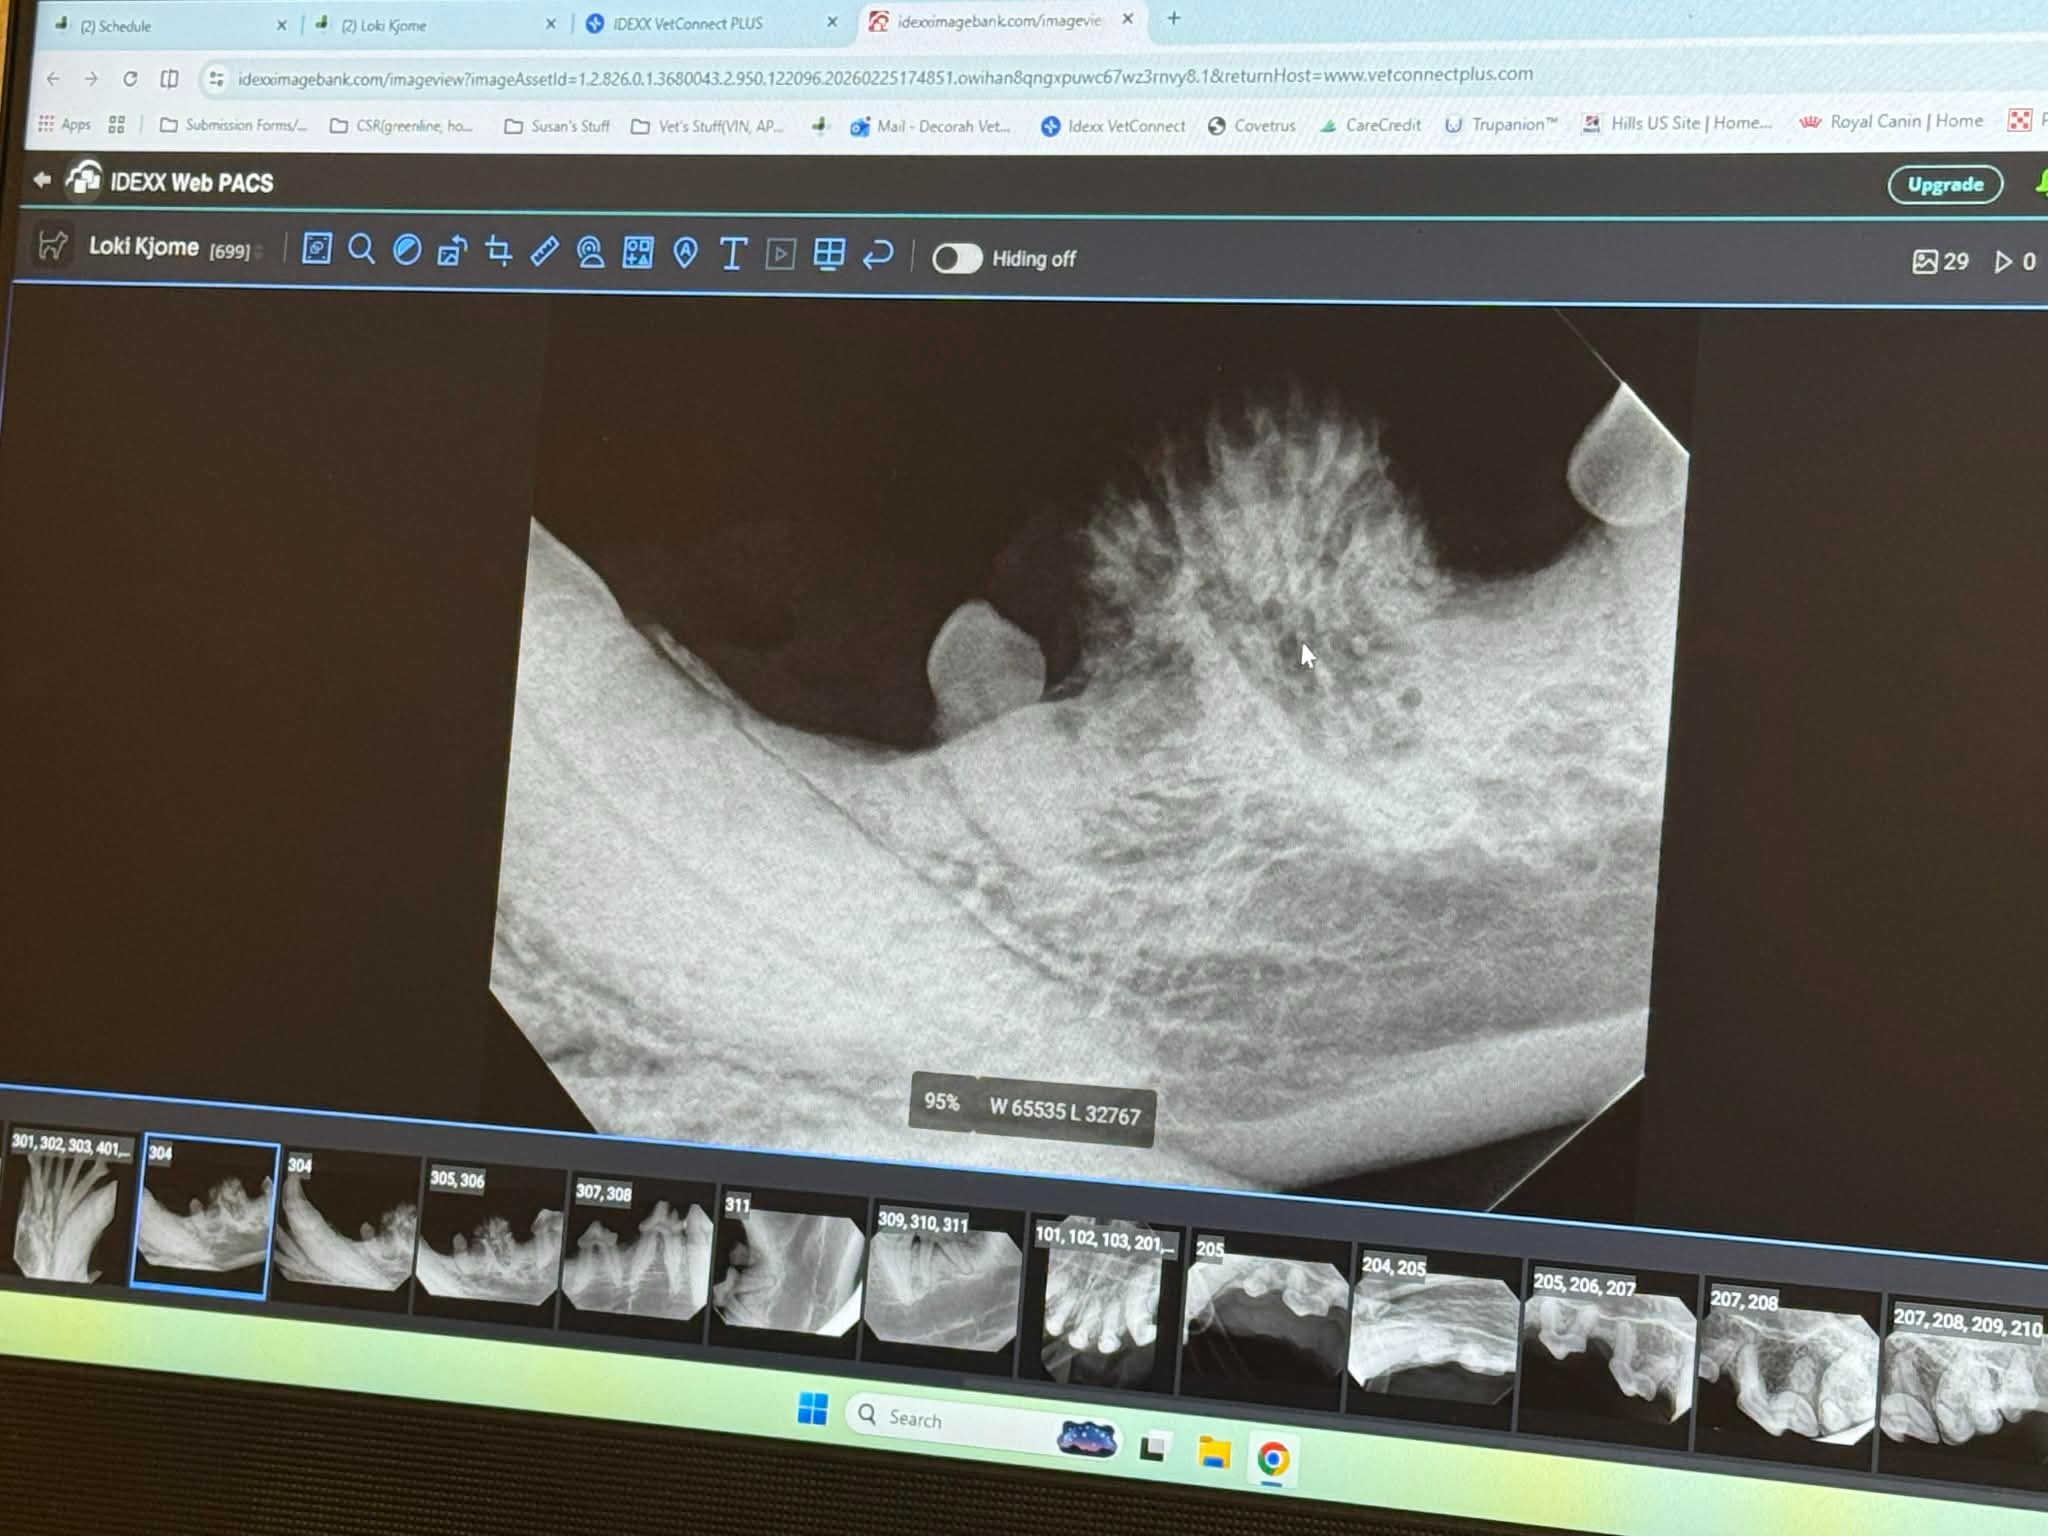

Our beloved Loki was recently diagnosed with an aggressive tumor on her jaw called acanthomatous ameloblastoma. Hearing this news has been devastating, as she has already shown so much strength and resilience in her life (having previously undergone two hip surgeries).